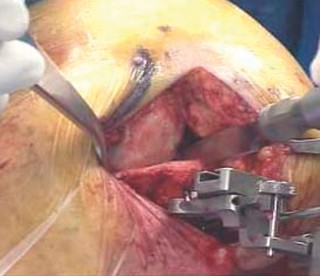

2. الوضع الجراحي والتعرض

- الوضع: يُوضع المريض في وضع الاستلقاء (Supine positioning) مع وضع كيس رمل أسفل الركبة أو حامل للساق يسمح بثني وفرد الركبة. يجب أن يكون الوضع مماثلاً لوضع جراحة TKA، مع استعداد لتحويل الإجراء إلى TKA إذا لزم الأمر.

- العاصبة (Tourniquet): تُستخدم عاصبة وتُوضع في أعلى الفخذ لتقليل النزيف.

-

الشق الجراحي:

يُستخدم شق طولي في الجانب الإنسي (الداخلي) من الركبة. يجب أن يكون الشق كبيرًا بما يكفي لتوفير رؤية جيدة للمفصل الرضفي الفخذي وإمكانية التحويل إلى TKA.

- فتح المفصل (Arthrotomy): يكون الفتح خطيًا وموازياً لألياف الوتر الرضفي، ويمتد إلى عظم الظنبوب وإلى الجزء السفلي من الرضفة.

- تحرير الأنسجة الرخوة: يتم قطع الغضروف الهلالي لتحرير الأنسجة الرخوة من عظم الظنبوب، ويتم تطوير سديلة تحت السمحاق في نمط دائري حول الظنبوب. يُمدد هذا التحرير خلفيًا لضمان توازن الأربطة.